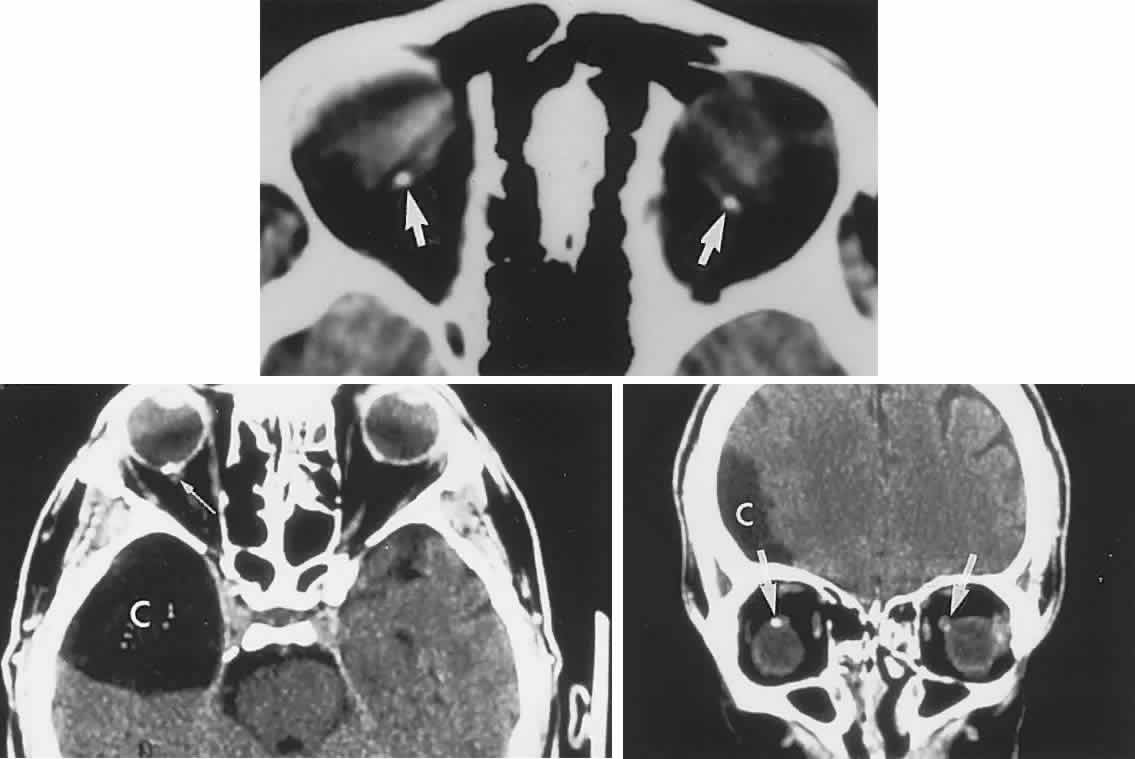

In contrast to transient symptoms and signs of retinal microembolic episodes, a condition of chronic ocular hypoxia (ocular ischemic syndrome) occurs less frequently, resulting from diffuse vascular occlusive disease of the aortic arch or common carotid artery. Acute or chronic occlusion with insufficient collateralization produces an ischemic pseudo-inflammatory uveitis, which variably includes an injected painful globe, corneal edema, aqueous flare and cells, a mid-dilated fixed pupil, rubeosis and iris atrophy, rapidly advancing cataract, either hypotony or elevated intraocular pressure (“neovascular glaucoma”), retinal microaneurysms and new vessel formation, posterior pole and mid-peripheral blot hemorrhages, macular edema, venous dilation and “sausaging,” cytoid infarcts (cotton-wool spots) of the nerve fiber layer, and arterial occlusions (Fig. 7; see Table 4). The hypoxemic fundus changes constitute a picture of venous stasis (low-pressure) retinopathy, perhaps the commonest ocular sign of chronic carotid obstruction.

Fig. 7. Ocular hypoxia with subacute carotid occlusion. The patient complained of a painful red eye. A. Anterior segment shows an irregular, fixed pupil and iris rubeosis (arrows). B. Fundus demonstrates combined retinochoroidal infarction with acute excavation of the optic disc. Arteriography revealed right internal carotid occlusion.

Ischemic photoreceptor metabolism accounts for subjective afterimages following exposure to bright light, including a positive photostress test60 (see Volume 2, Chapter 2). Low retinal arterial pressure may be detected by observing pulsation or collapse of the disc arterioles with even slight fingertip pressure exerted on the globe. Such borderline perfusion associated with carotid stenosis and retinopathy may be heralded by postprandial visual loss.61 In the situation of chronic, subacute, or rapidly progressive ischemic oculopathy, giant cell arteritis must be considered in the differential diagnosis, and chronic venous obstruction or diabetic retinopathy may produce similar fundus appearance.